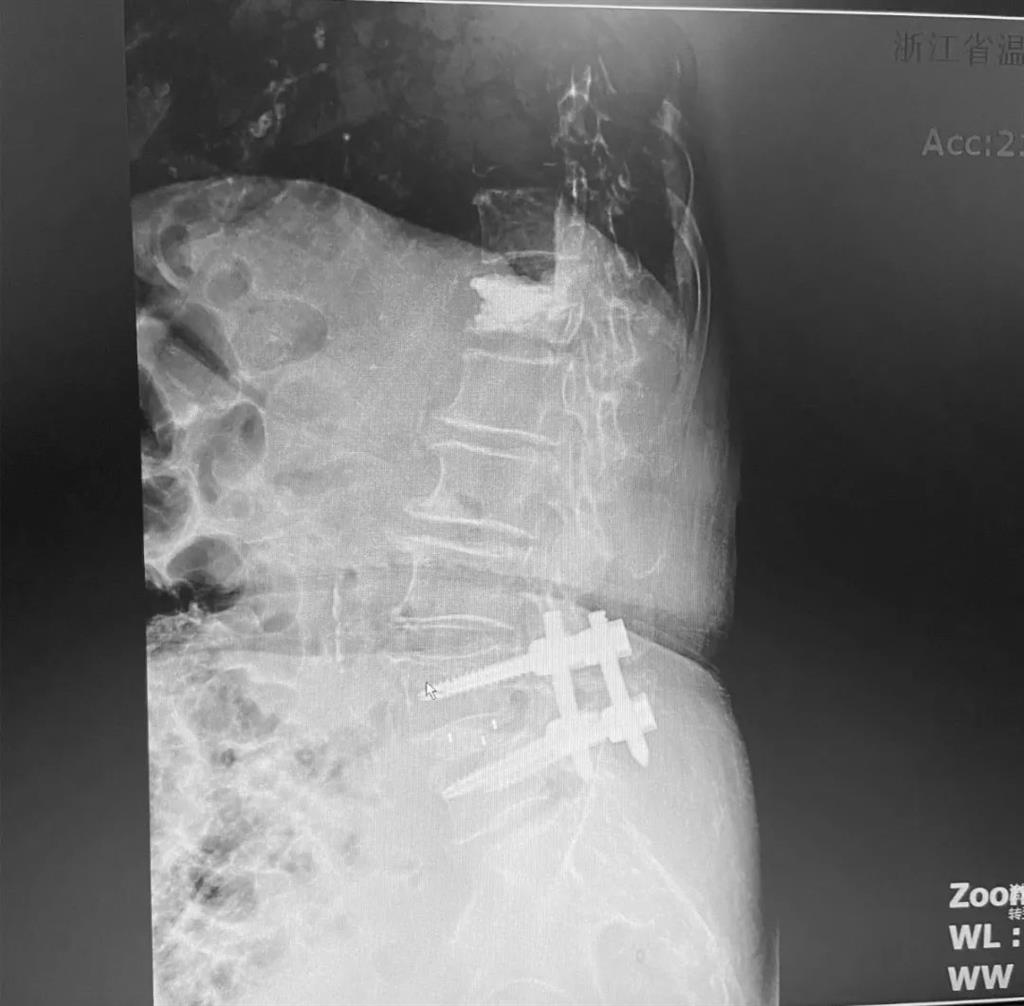

劉丹主任表示,傳統(tǒng)手術(shù)需要廣泛剝離脊椎兩側(cè)的肌肉,術(shù)后容易產(chǎn)生疤痕、肌肉萎縮、腰部疼痛等;術(shù)中出血多,往往需要額外輸血,另外創(chuàng)傷大的同時也容易破壞脊椎的正常結(jié)構(gòu),對于老年人、體弱的人群來講,恢復(fù)期長、風(fēng)險多。

而脊柱內(nèi)鏡下腰椎融合術(shù),作為目前國內(nèi)脊柱微創(chuàng)領(lǐng)域大力發(fā)展的新技術(shù),徹底改變了傳統(tǒng)開刀椎板切除椎間植骨融合內(nèi)固定的大創(chuàng)傷現(xiàn)狀,可以在較大程度上減少對脊柱后方穩(wěn)定結(jié)構(gòu)的破壞,創(chuàng)傷小,出血少,術(shù)后恢復(fù)快。

非常適用于體質(zhì)較差不能耐受開放手術(shù)的老年患者,且手術(shù)全程均在內(nèi)鏡監(jiān)測下進(jìn)行,能夠最大程度地避免硬膜囊和神經(jīng)根損傷,手術(shù)安全性更高。